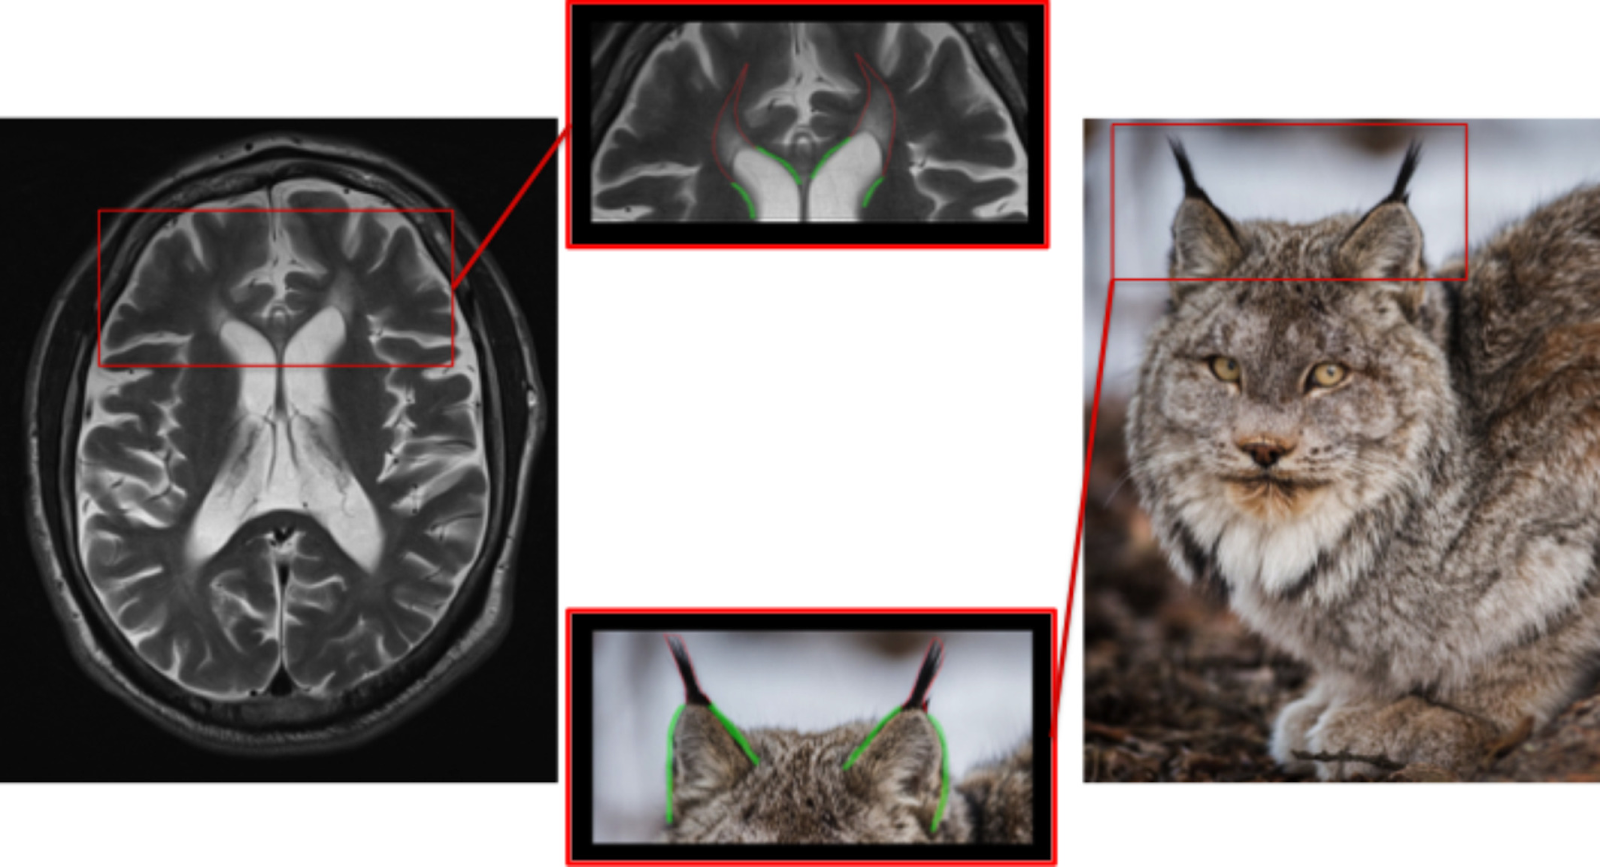

6) Ears of the Lynx

Clinical Correlate: Hereditary Spastic Paraplegia (SPG 11 + 15)